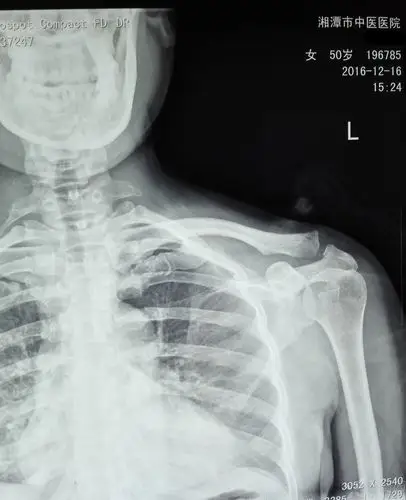

肩锁关节脱位的保守治疗 [病例帖]